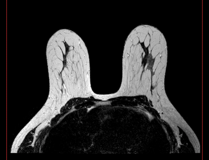

Standardized body region labelling of individual images provides data that can improve human and computer use of medical images. A CNN-based classifier was developed to identify body regions in CT and MRI. 17 CT (18 MRI) body regions covering the entire human body were defined for the classification task. Three retrospective databases were built for the AI model training, validation, and testing, with a balanced distribution of studies per body region. The test databases originated from a different healthcare network. Accuracy, recall and precision of the classifier was evaluated for patient age, patient gender, institution, scanner manufacturer, contrast, slice thickness, MRI sequence, and CT kernel. The data included a retrospective cohort of 2,934 anonymized CT cases (training: 1,804 studies, validation: 602 studies, test: 528 studies) and 3,185 anonymized MRI cases (training: 1,911 studies, validation: 636 studies, test: 638 studies). 27 institutions from primary care hospitals, community hospitals and imaging centers contributed to the test datasets. The data included cases of all genders in equal proportions and subjects aged from a few months old to +90 years old. An image-level prediction accuracy of 91.9% (90.2 - 92.1) for CT, and 94.2% (92.0 - 95.6) for MRI was achieved. The classification results were robust across all body regions and confounding factors. Due to limited data, performance results for subjects under 10 years-old could not be reliably evaluated. We show that deep learning models can classify CT and MRI images by body region including lower and upper extremities with high accuracy.

翻译:个人图像标准化体格标签提供了可以改进人体和计算机医疗图像使用的数据; 开发了一个CNN的分类器,以确定CT和MRI的人体区域; 为分类任务确定了覆盖整个人体的17个CT(18MRI)机构区域; 为AI模型培训、验证和测试建立了三个追溯数据库,每个机构区域的研究分布均衡; 测试数据库来自不同的保健网络; 对病人年龄、病人性别、机构、扫描机制造商、对比、切片厚度、MRI序列和CT内核的分类器进行了准确、回顾和精确性评价; 数据包括2 934个匿名CT案例的追溯组(培训:1 804项研究、验证:602项研究、测试:528项研究)和3 185个匿名MRI案例(培训:1 911项研究、验证:636项研究、测试:638项研究)。 初级护理医院、社区医院和成像中心27个机构对测试数据集进行了准确性评估; 数据包括:92%以上的性别比例和科目的追溯性案例; 95年的高级和90个高等级数据序列,显示为91至90区域。